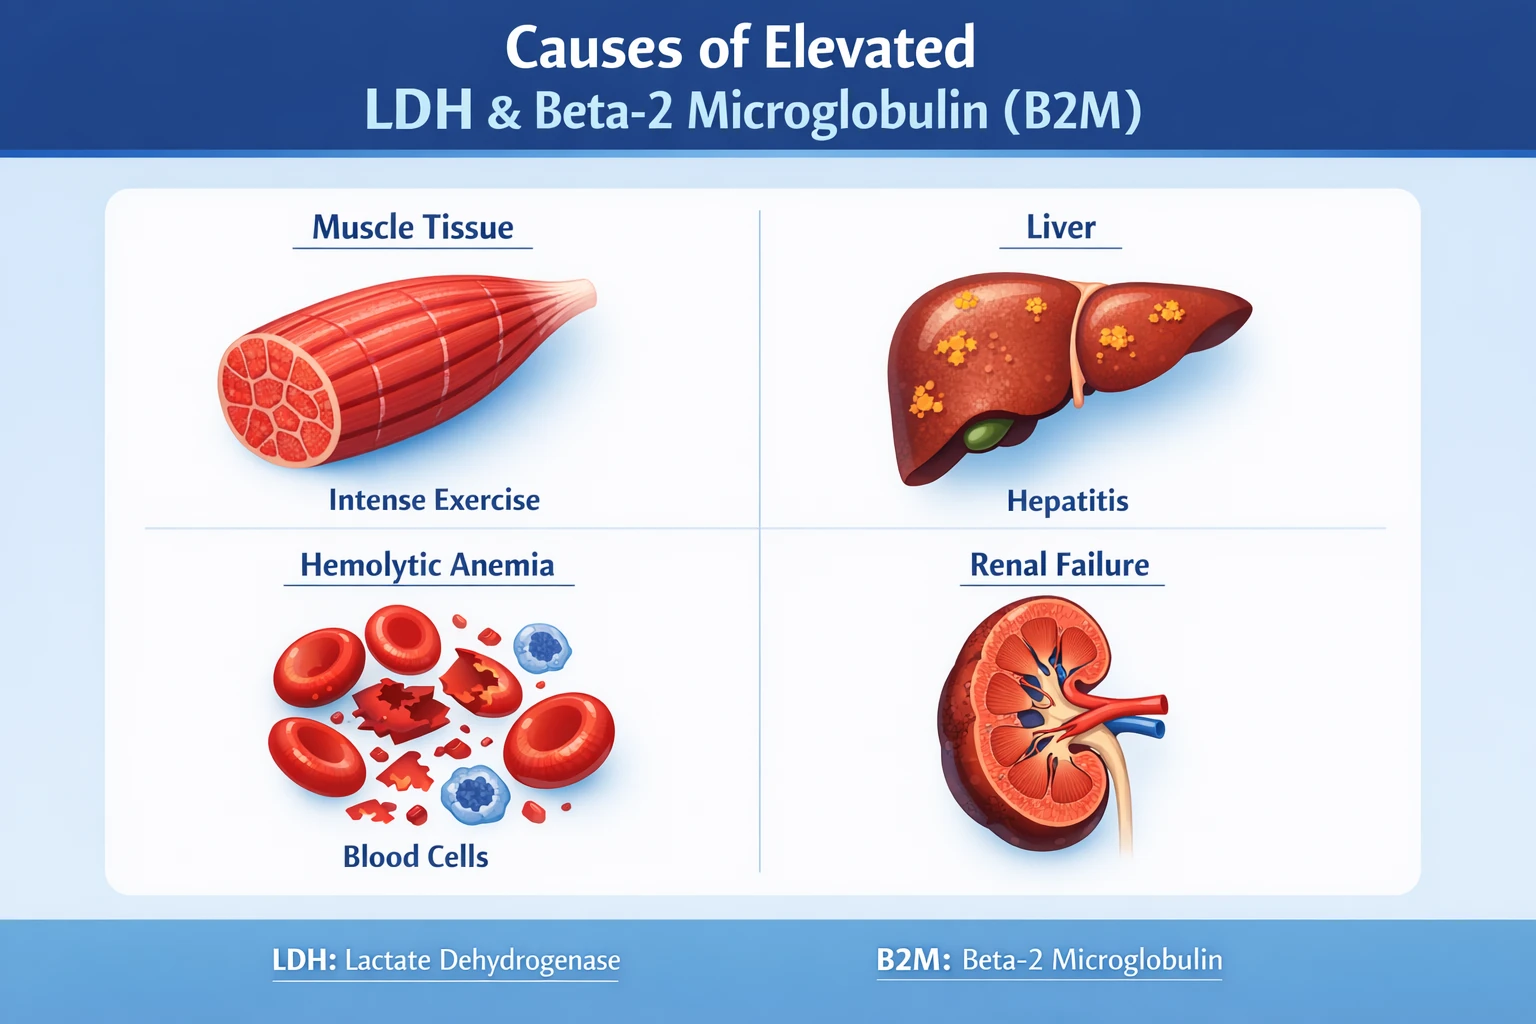

- عدم اختصاصی بودن: سطح SCC ممکن است در بیماریهای غیرسرطانی مانند پسوریازیس، آسم یا اگزما نیز افزایش یابد.